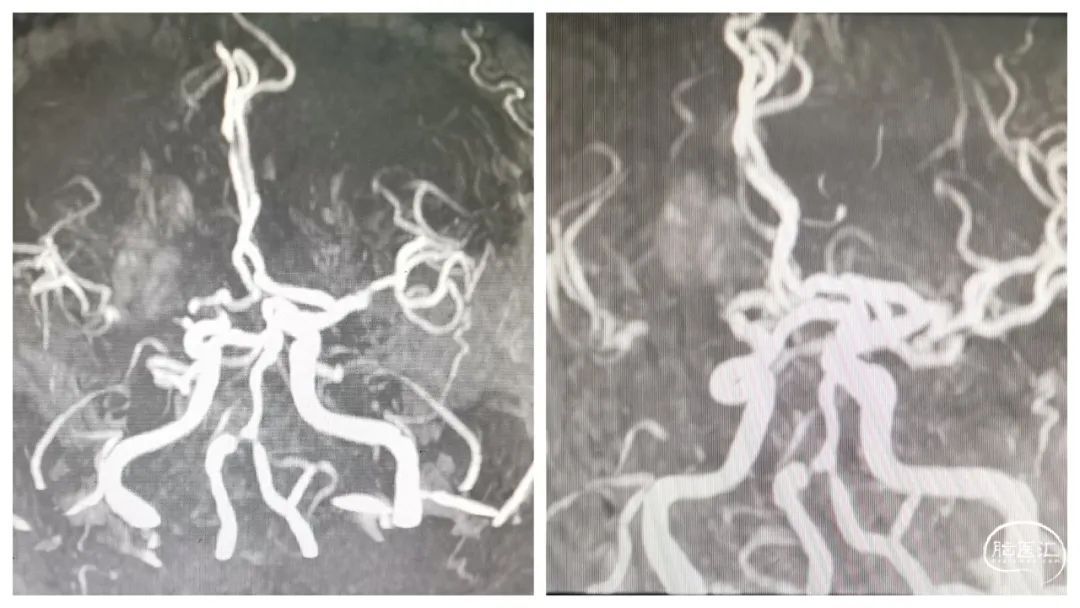

MRA显示右侧大脑中动脉狭窄严重。

DSA显示右大脑中动脉重度狭窄,狭窄率约90%。

右大脑中动脉极重度狭窄(支架植入后再狭窄)。